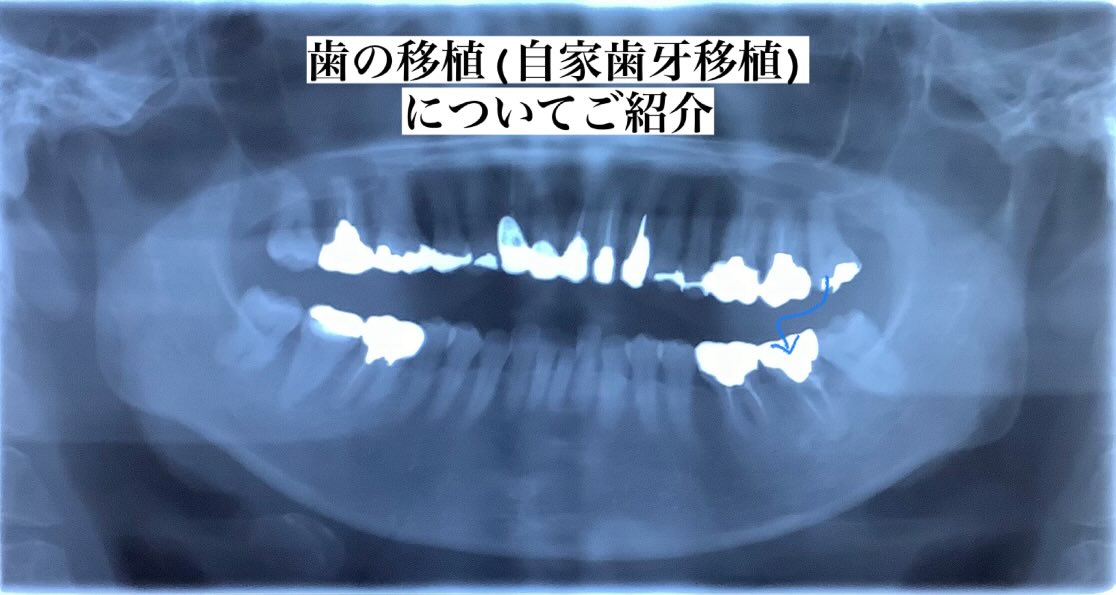

こんにちは♪北都歯科クリニックです🍀 今回は歯の移植という治療についてご説明します むし歯が進行してしまったり、根っこのハセツなどで抜歯が必要なった場合 ブリッジや入れ歯という選択肢が考えられますが 健康な両サイドの歯を削る、入れ歯のバネが目立つなどデメリットも存在します